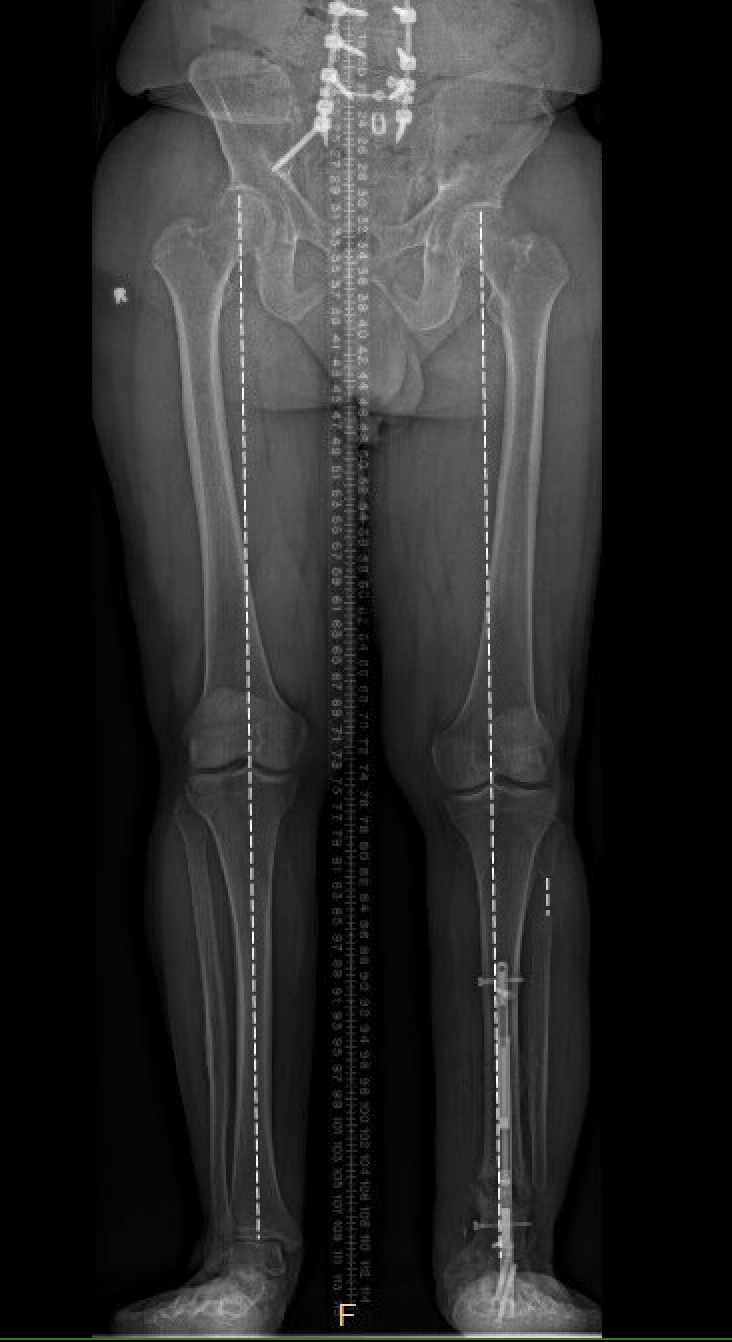

The operation took place in November 2022. Because Natale’s ankle was fused, Marecek chose to lengthen Natale’s tibia, or shin bone, rather than his femur. Marecek also identified that Natale’s ankle had been fused out of alignment. So, first he corrected the ankle’s alignment, then he broke Natale’s tibia and inserted a distraction rod—the kind that could push the two sides of the broken bone apart.

Natale could not put any weight on the leg for three months. After that the distraction rod was removed and replaced by a weight-bearing rod.

The amount of time the process takes depends on the amount of lengthening and whether more than one limb is involved. Since the rods are not weight bearing, sometimes legs are lengthened separately, which increases the overall time it takes.

Natale says he had to do a lot of physical therapy, stretching the muscles to make space for the longer leg bone. It was about six months before Marecek gave him the go-ahead to put his full weight on it. Even after a year, X-rays showed the bone still hadn’t completely filled in the gap around the rod in his tibia.